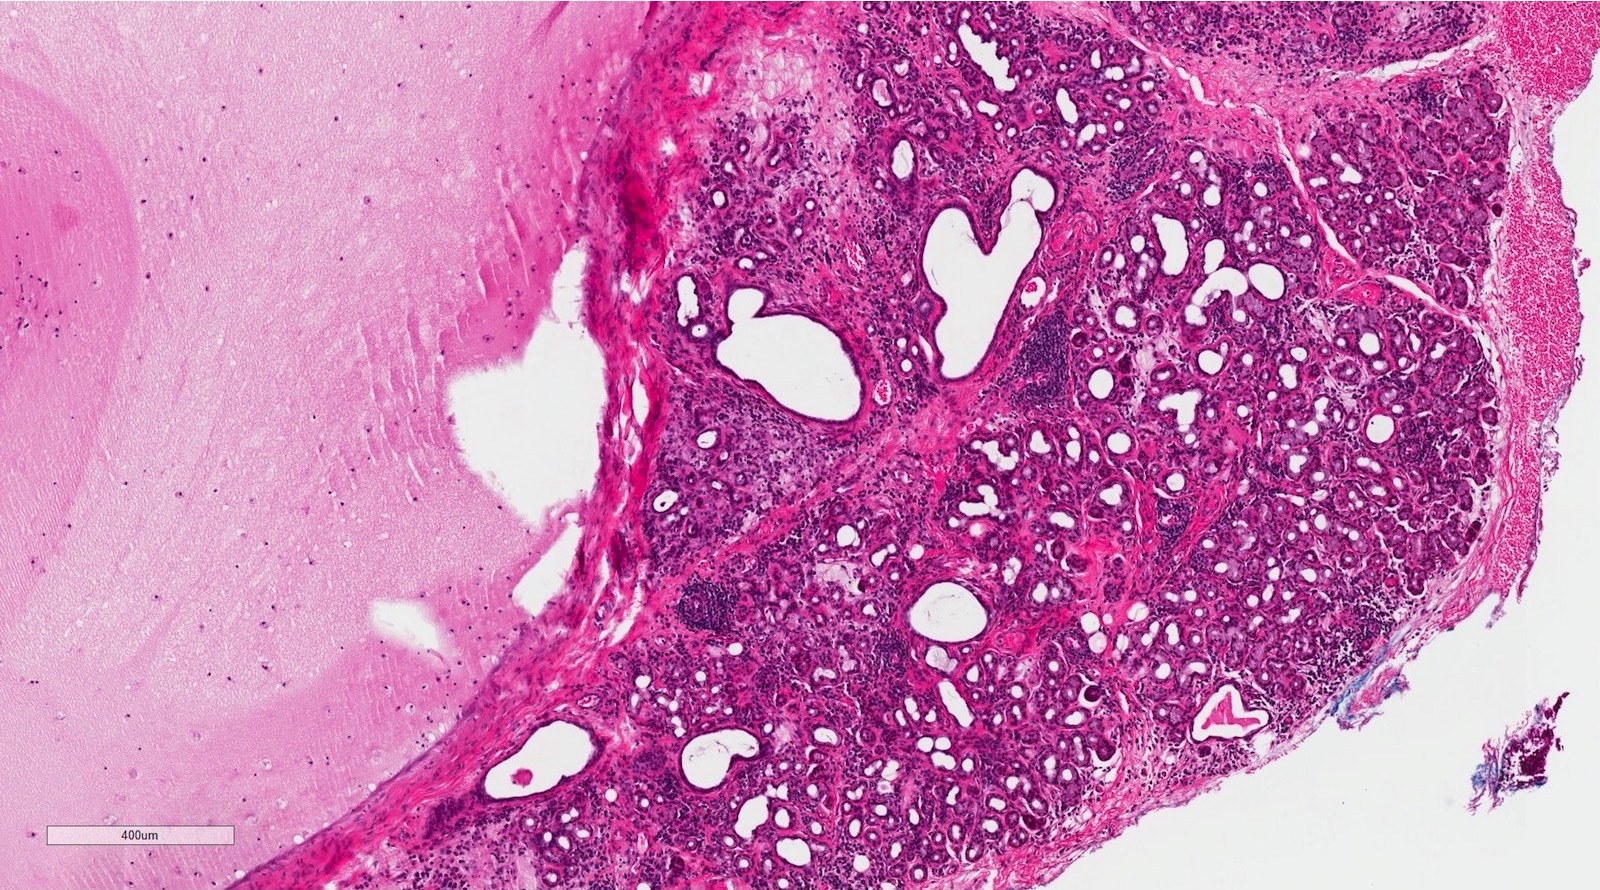

Microscopic (histologic) description

- If removed intact

- Pseudocyst cavity containing mucin, abundant epithelioid foamy histiocytes (muciphages), neutrophils and granulation tissue (Acta Histochem 2014;116:40)

- Removed salivary gland parenchyma showing obstructive changes

- Acinar atrophy, ductal dilatation with periductal hyalinization, interstitial lymphoplasmacytic infiltrate and interstitial fibrosis at late stage (J Oral Maxillofac Surg 2008;66:2050)

- May see ruptured feeding salivary duct with squamous metaplasia (J Oral Maxillofac Surg 2008;66:2050)

- Long standing lesions organize into fibrosis resembling a fibroepithelial polyp (Acta Histochem 2014;116:40)

- No epithelial cyst lining, may see overlying surface oral mucosa with variable atrophy in superficial mucoceles (J Oral Maxillofac Surg 2011;69:1086)

Microscopic (histologic) images